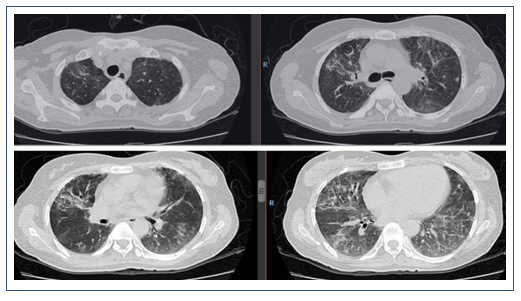

2019年1月25日,患者胸部CT显示双下肺实变较前有所吸收(图11)。

图11 2019年1月25日患者胸部CT

2019年2月1日患者胸部CT显示,上肺渗出进展(图14)。

2019年2月25日患者胸部CT示双肺病变较前吸收(图16)。